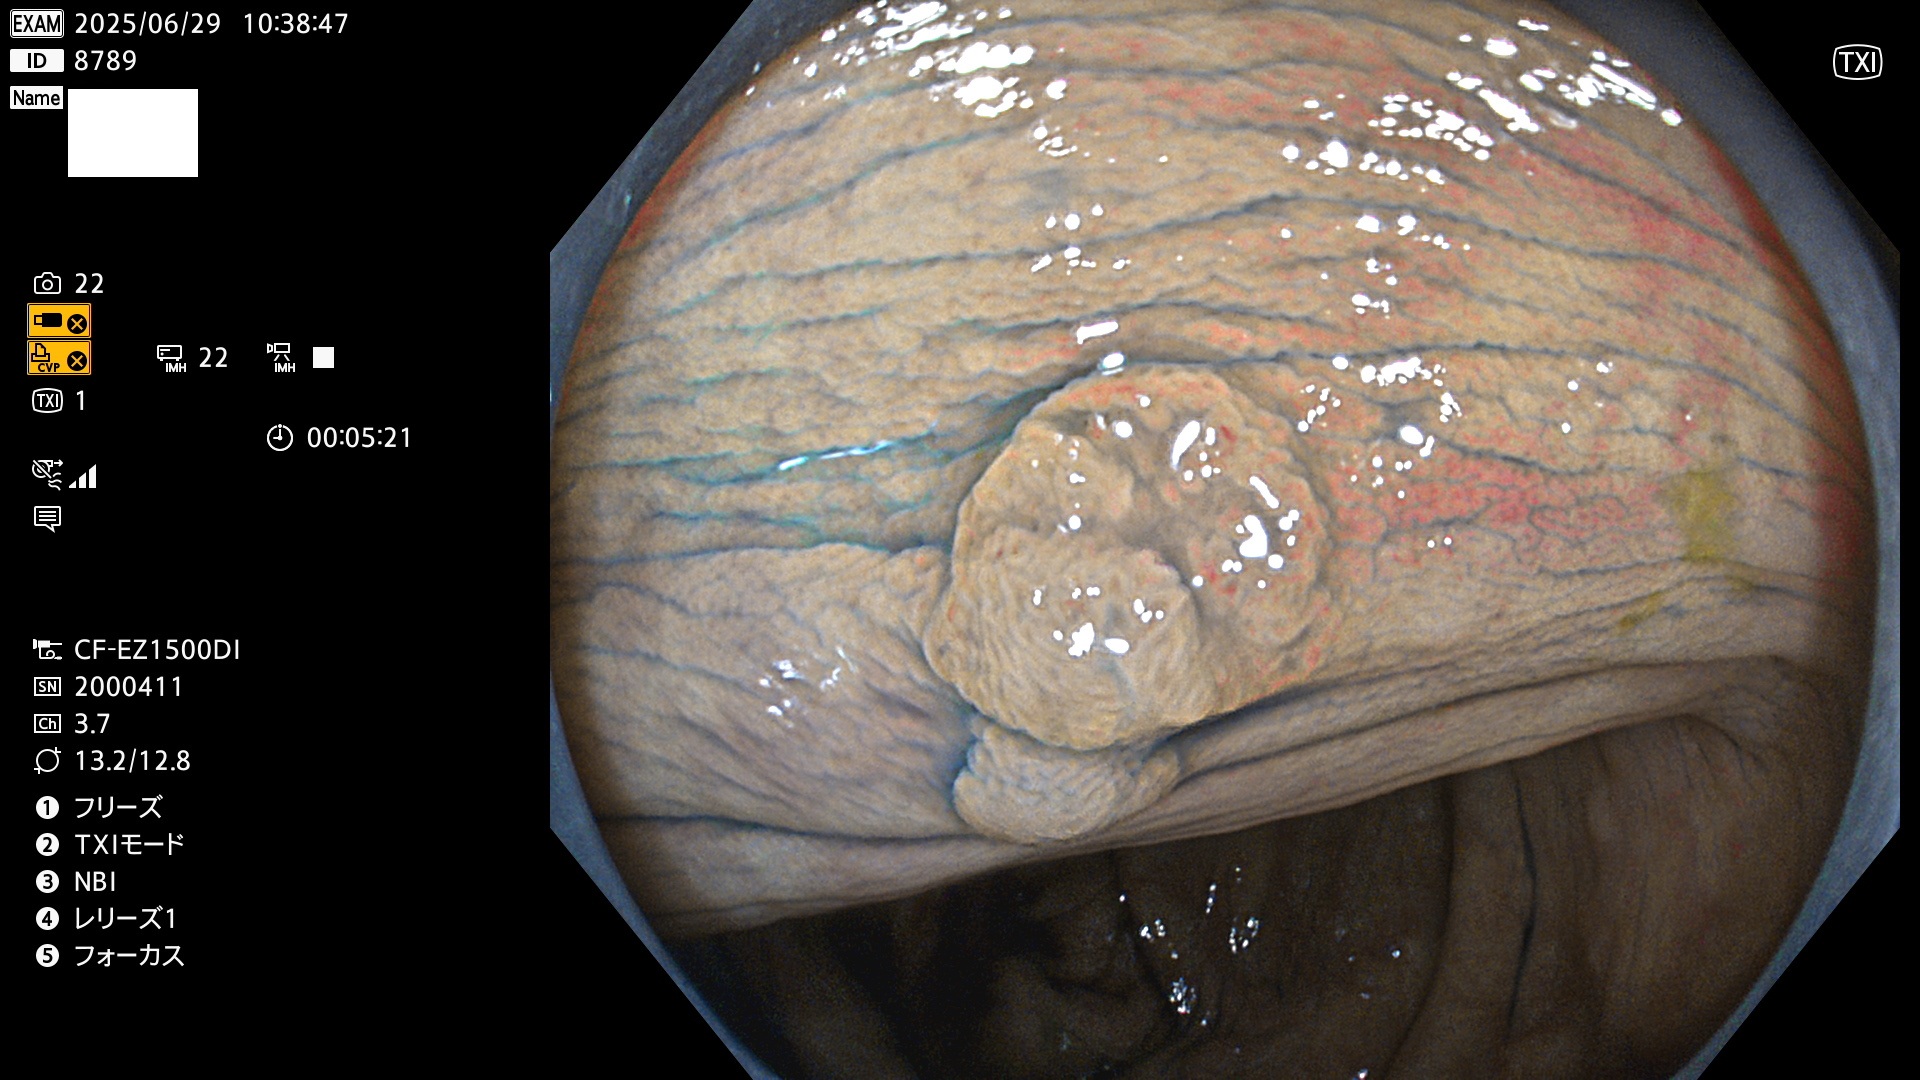

完全に平坦な物をUb、陥凹している物をUcと呼びます。Ubは認識が困難で、Ucはびらん(炎症)と紛らわしいために見落とされやすく、「内視鏡後・大腸癌」の原因になります。

毎週の検査(木・金・土・日)に発見されたUb、Uc型・腺腫を、その週の日曜の夜にUPし1週間、提示します。

抽出の対象期間 2025年6月26日〜6月29日の4日間(40件の検査)7個 (7/40=18%)